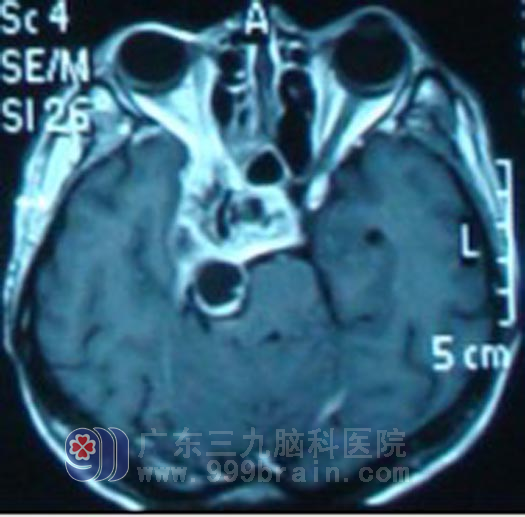

今年3月,吴先生再次出现恶心,并伴有右眼视力下降,再次复查鼻咽CT提示肿瘤较2010年5月有所增大。4月11日,吴先生在外院就诊过程中突发烦躁,胡言乱语,四肢不自主活动等症状,急诊送入广东三九脑科医院肿瘤综合治疗中心求进一步治疗,来院后急行CT示:右侧海绵窦占位性病变,压迫脑干,脑室扩大、脑积水。4月12日急诊在全麻下行脑室外引流术,4月13日开始行急诊放疗,病情逐渐好转。4月18日拔除引流管,吴先生已无烦躁胡言乱语症状,未出现头痛恶心呕吐等不适。随后行复发肿瘤区域成放疗及辅助化疗。现在吴先生康复良好,肿瘤基本消失,定期会院复查。http://www.999brain.com/

放疗前